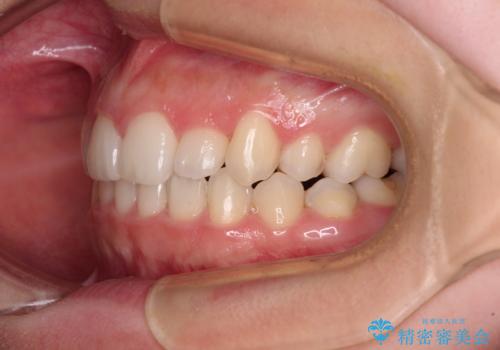

- 前歯のデコボコと八重歯を気にして来院された患者様です。

目立たない装置を希望されたので、上顎が裏側装置のハーフリンガルを選択し、左右上顎小臼歯1本ずつを抜歯して、矯正治療を行うこととしました。